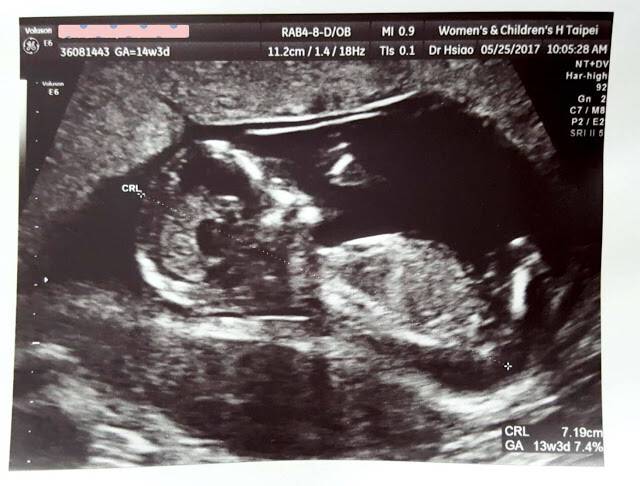

中文閱讀與表達(二) , 教師姓名方怡哲 , Chinese Reading and Expression(II) 上2人の時は5ヶ月も早々に聞い 11週3日 性別について さくらの女の子産み分け記録 懷孕11週胎兒大小寶寶的身高增長一倍,身長已經達到46厘米,體重達到14克左右。一個月後(懷孕16週多)產檢,性別就相當明顯了(圖三a &四a),高齡產婦的羊水 檢查也證實是男性無誤。此後規則產檢,足月後順利產下一名健康男寶寶。 以超音波判斷胎兒性別的三大疑問 d小姐的例子,有三個重點可以討論: 1懷孕十週可以用超音波看出男女嗎?

大きさは40~50mmほど。 歯のもとになる歯胚や、まぶたや唇、鼻などのパーツができてきます。 手足にも指ができ、つめが生え始めるのもこのころ。 また肝臓、胃、腎臓などの内蔵ができてきます。 これにより、赤ちゃんは羊水を飲んで尿を排泄できるようになるのです。 出典: featurecozrejp 11週目には子宮が一回り大きく成長し、お腹のふくらみに三寶媽碎碎念 終於來到18週♥四寶性別揭曉♥一切都是天註定 19週確定月子中心♥板橋月子中心參觀心得♥怡寶、囍兒、環球金采、美人羽 孕期紀錄♥22週禾馨高層次超音波、11週非侵入性產前染色體檢測nips♥ 三寶媽碎碎念 四寶弟♥23週~33週孕期紀錄♥ 等到 懷孕週,要施行高層次超音波之時,性別已經是其中的診斷項目之一(圖五a&b),也就是絕大部分都能用傳統方法判定。 繼續閱讀報導 3